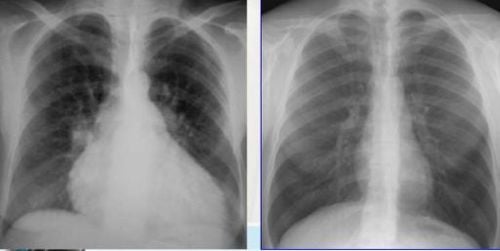

1. Bóng tim to

Để xác định bóng tim to trên phim chụp X-quang cần xác định tỷ lệ tim ngực, chỉ số tim ngực là tỷ lệ giữa kích thước chiều ngang của bóng tim và kích thước chiều ngang lồng ngực. Bóng tim bình thường trên phim chụp tim phổi thẳng có tỷ lệ tim ngực là từ 0,5-0,55. Bóng tim to khi tỷ lệ tim ngực lớn hơn 0,55.

Hình ảnh bóng tim to trên X quang